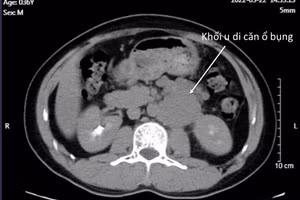

GD&TĐ - Bệnh nhân nam bị ung thư tinh hoàn đã phẫu thuật và sử dụng hóa trị nhưng khối u di căn trong bụng ngày càng to chiếm hết ổ bụng. Bác sĩ vẫn quyết định phẫu thuật cứu chữa dù rủi ro rất cao.